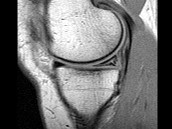

- 单项选择题男,29岁, 左膝关节有外伤史,膝关节疼痛, 活动受限,结合所提供的图像, 最可能的诊断是 ( )

B、前十字韧带撕裂

C、内侧半月板外周后角垂直撕裂

D、内侧半月板后角撕裂

E、后十字韧带撕裂